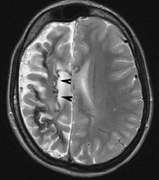

2. Subependymal nodules (SEN) are typically found along the lateral borders of the ventricles and parehncymal brain lesion (“cortical tubers”) (Figs. 14 and 15). Calcification in the first year of life is rare.132

On MRI imaging, the subependymal nodules and parenchymal brain lesions of infants (age ≤3 months) and adults show different signal characteristics. Infant CNS tubers are hyperintense on T1-weighted images and hypointense on T2-weighted images, which is the opposite of the pattern seen in adults.134 Malignant transformation of SEN occurs in about 10% to 15% of patients and the resultant subependymal giant cell astrocytoma accounts for 25% of premature deaths in TSC.135,136

Fig. 14. Tuberous Sclerosis Complex: Sub-Ependymal nodules. These are typically found along the lateral borders of the ventricles.132

Fig. 15. Tuberous Sclerosis Complex. (a) Patient 1: Axial CT scans demonstrating typical calcification of subependymal nodules in a 13-year-old girl with a history of seizures. (b and c) Patient 2. (b) Axial T2-weighted images demonstrate calcified subependymal nodules (arrowheads) and cortical tubers typical of tuberous sclerosis. (c) Widespread cortical tubers are seen on a coronal FLAIR sequence as thickening of the cortex and high signal of the subcortical white matter.